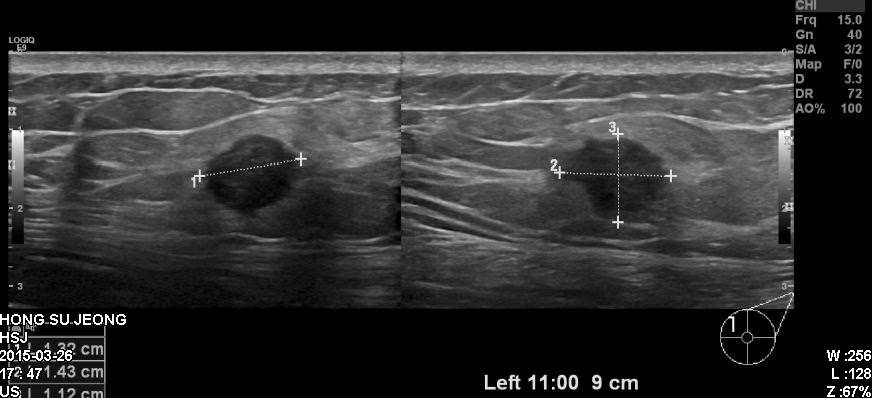

건진상 이상소견으로 내원하신 50대 환자분이십니다.

본원에서 좌측 유방 11시방향에 있는 혹 조직검사시행하였고

침윤성유관암 진단되었습니다.